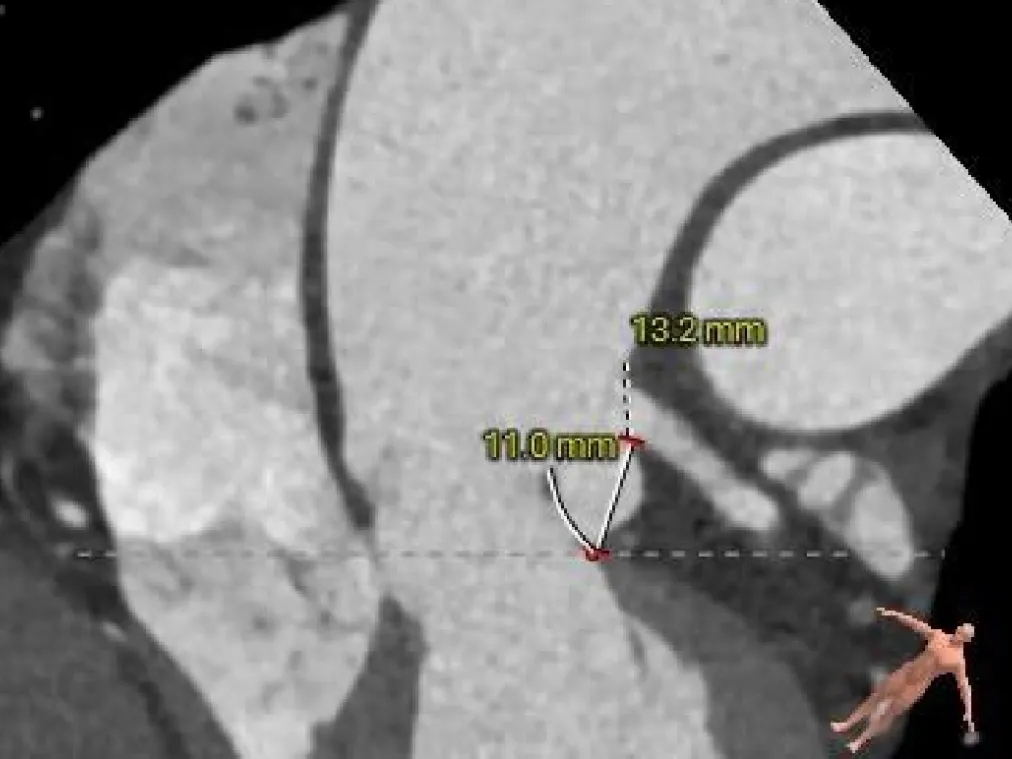

三叶式主动脉瓣,瓣叶未见明显增厚及钙化,收缩期瓣环周长径约为23.6mm,流出道周长径约为21.9mm,LVOT呈收口状,舒张期瓣环周长径约为21.9mm,流出道周长径约为22.9mm;

双侧冠脉开口高度可,左窦瓣叶切线测量距离<冠脉开口下缘到根部距离;

主动脉根部测量

Annulus

23.6mm

LVOT

21.9mm

瓣上结构测量

Annulus:

24.5mm

瓣上4mm:

24.9mm

瓣上6mm:

26.6mm

瓣上8mm:

27.1mm

瓣上10mm:

27.5mm

未见明显钙化